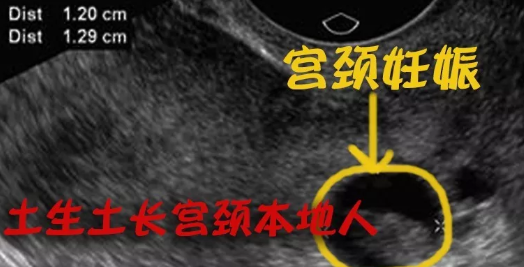

宮頸妊娠

宮頸妊娠是懷孕女性容易碰到的疾病問題,那么有關宮頸妊娠的疾病怎么治療,宮頸妊娠對胎寶寶的影響大嗎,下面八寶網就帶來專題介紹:宮頸妊娠。..